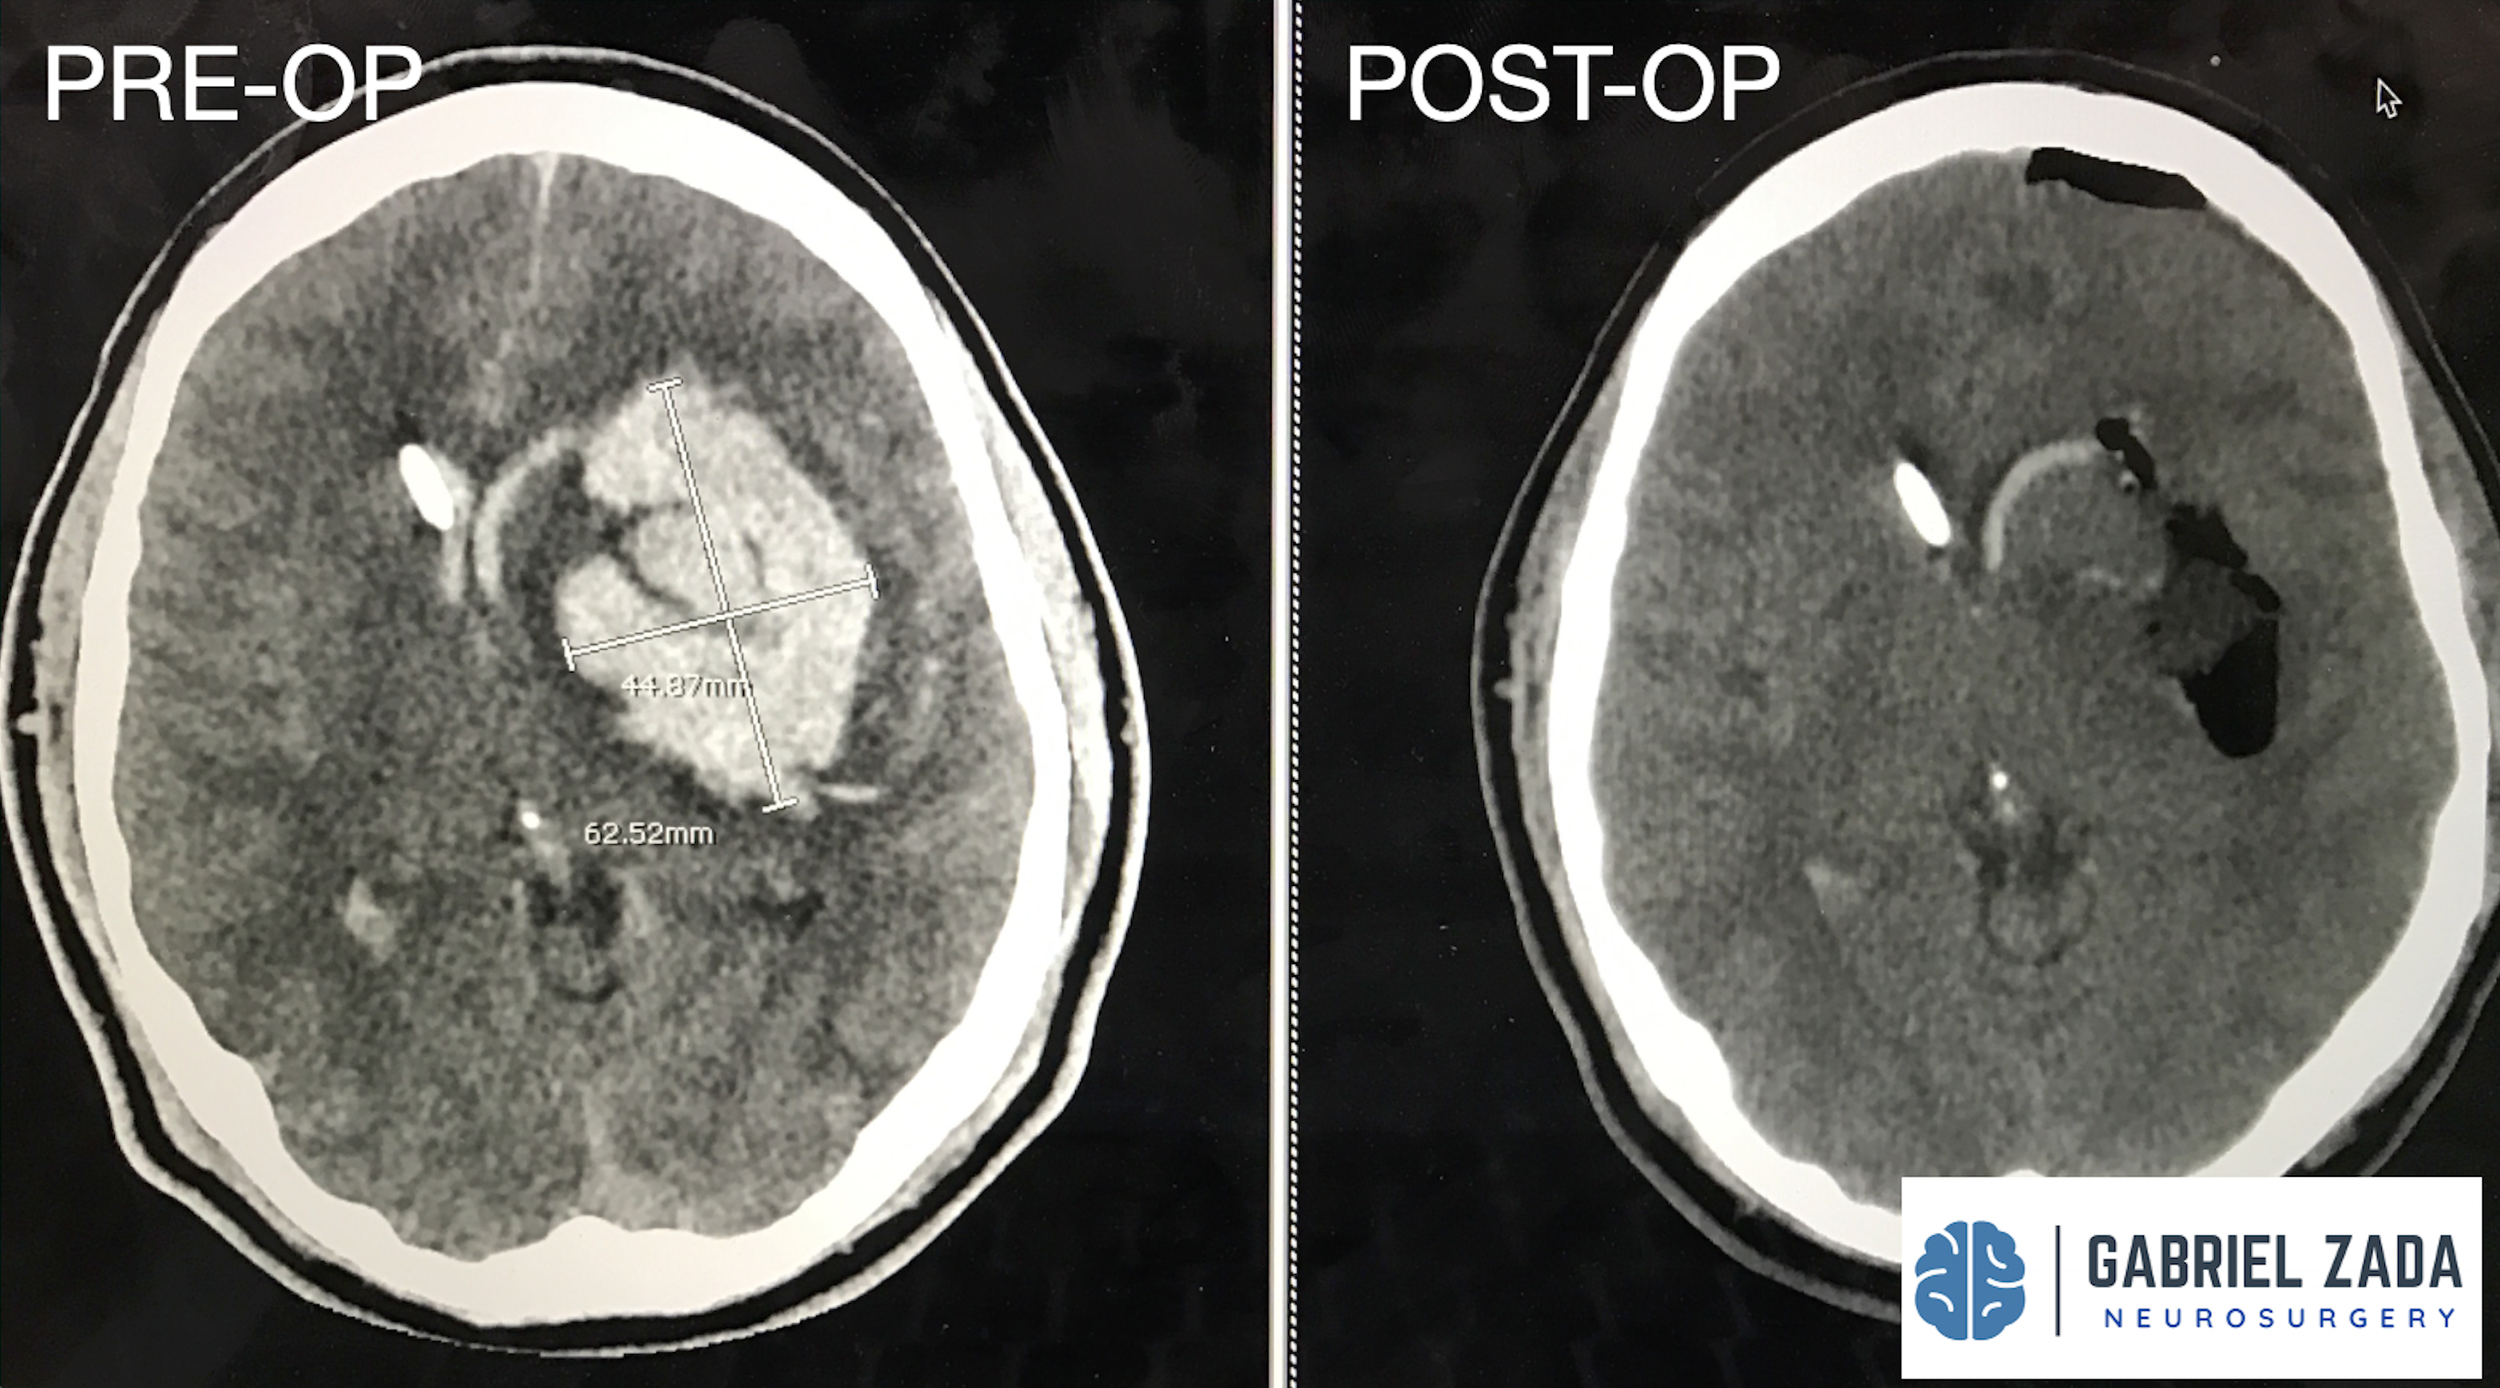

Explore this comprehensive gallery featuring pre‑ and post‑operative imaging of patients with skull‑base tumors treated by Gabriel Zada, MD, MS, FAANS, FACS. These cases highlight Dr. Zada’s expertise in advanced neurosurgical techniques and outcomes.

*Representative cases shown for educational purposes. All images de-identified. Individual results vary.